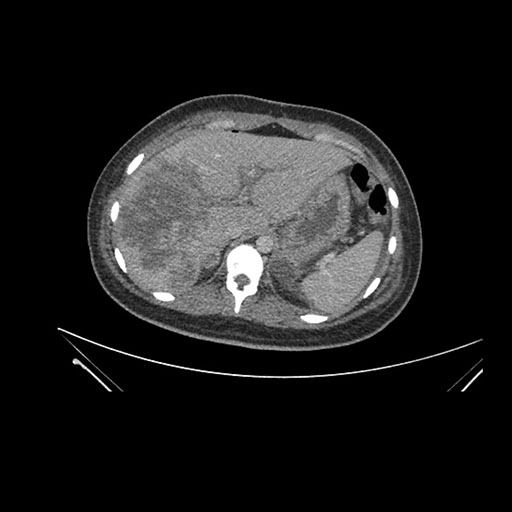

Imaging Analysis

Look through the patient's CT scan to identify any areas of concern for the necessary procedure.

Axial Venous

Based on initial findings, which issue(s) would you be most concerned about?